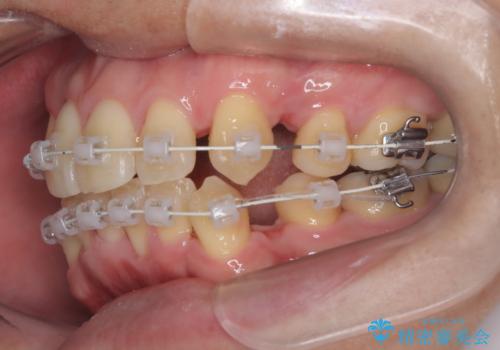

- 矯正装置

- ワイヤー(審美装置)

- 2年2ヶ月

- 10-30回

デコボコの量が多かったため上下左右4を抜歯してワイヤー矯正で治療を行いました。